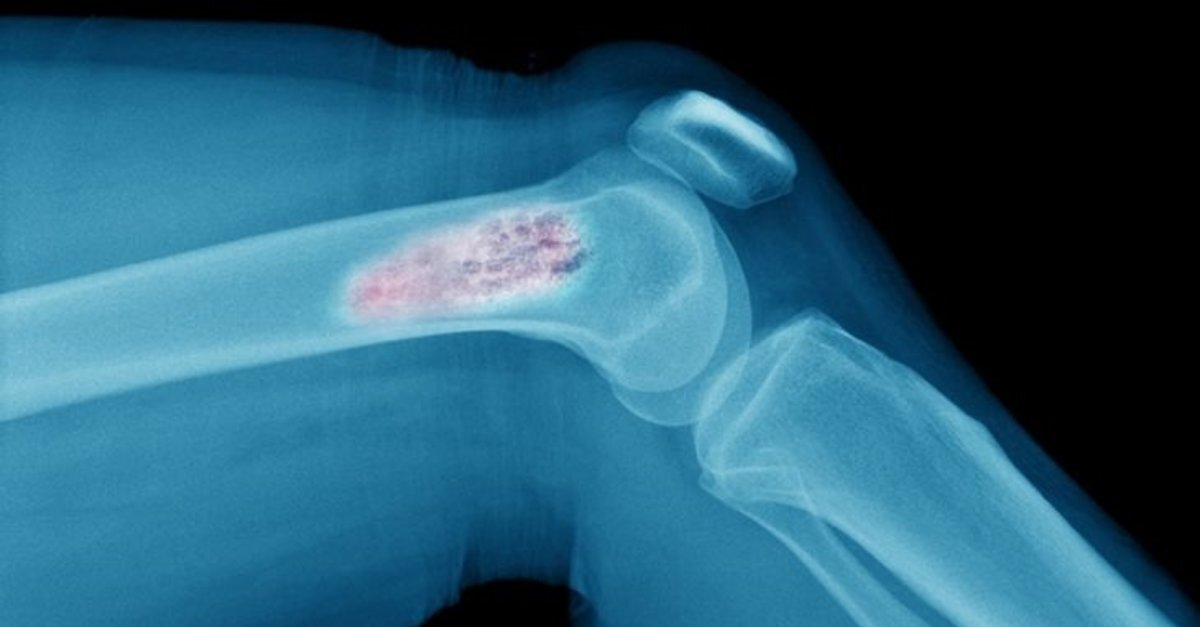

1. Остеосаркома

Рак кости - остеосаркома

Также называется остеогенной саркомой. Фактически, это наиболее распространённый тип рака костей, который обычно начинается в костных клетках рук и ног. Остеосаркома чаще всего встречается у людей в возрасте от 10 до 30 лет, чаще у мужчин, чем у женщин.